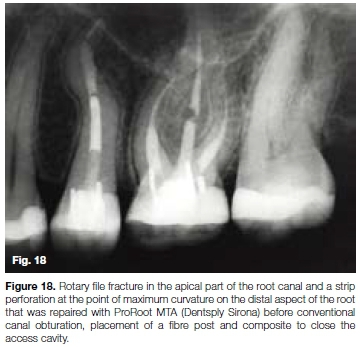

The patient, a 37 year old female presented with irreversible pulpitis on her maxillary left first second premolar. The tooth had been previously restored with a large composite resin restoration and two retention pins. A preoperative peri-apical radiograph (Figure 16) and a length determination radiograph (Figure 17) revealed and confirmed a challenging "S" shaped or bayonet-shaped root canal configuration.

Due to the lack of proper glide path preparation and management in this case, the operator was faced with a rotary file fracture in the apical part of the root canal and a strip perforation at the point of maximum curvature on the distal aspect of the root. It was impossible to even attempt the retrieval of the fractured instrument and it was left in situ.

After canal irrigation, the perforation was repaired with ProRoot MTA (Dentsply Sirona) before conventional canal obturation (Figure 18).

The access cavity was restored with composite resin and placement of a fibre post. Figure 19 shows a four-year follow up radiograph with some evidence of resorption of the extruded ProRoot MTA material.